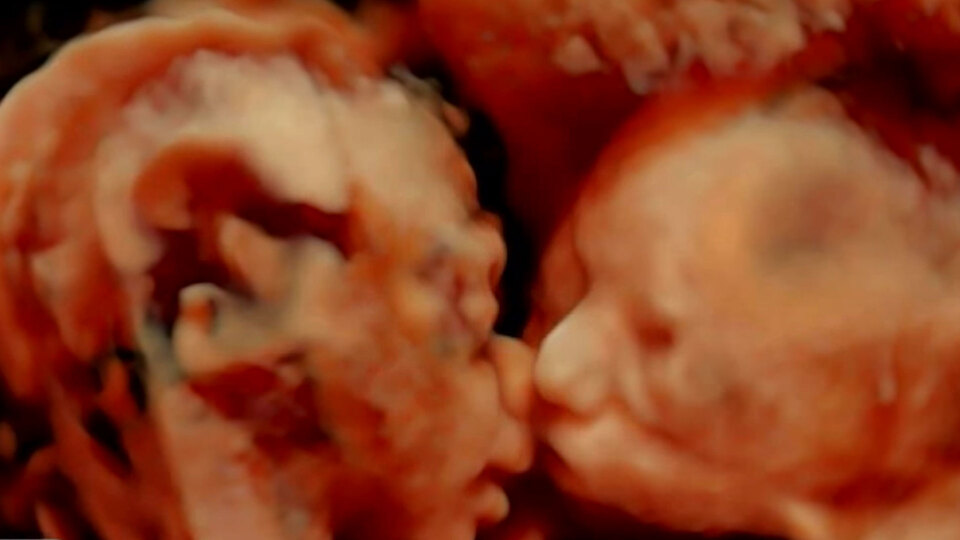

Kardeş sevgisi gibisi yok... Carissa Gill ve erkek arkadaşı Randy Goo, salı günü bebeklerini kontrol ettirmek için ultrason çektirmeye gittiler. Anne karnında sürekli kıpırdayan Isabella ve Callie bebeğin birbirlerini öptüğü tespit edildi. 25 haftalık bebekler anne, baba ve fotoğrafı gören herkesi şaşkınlığa uğrattı.